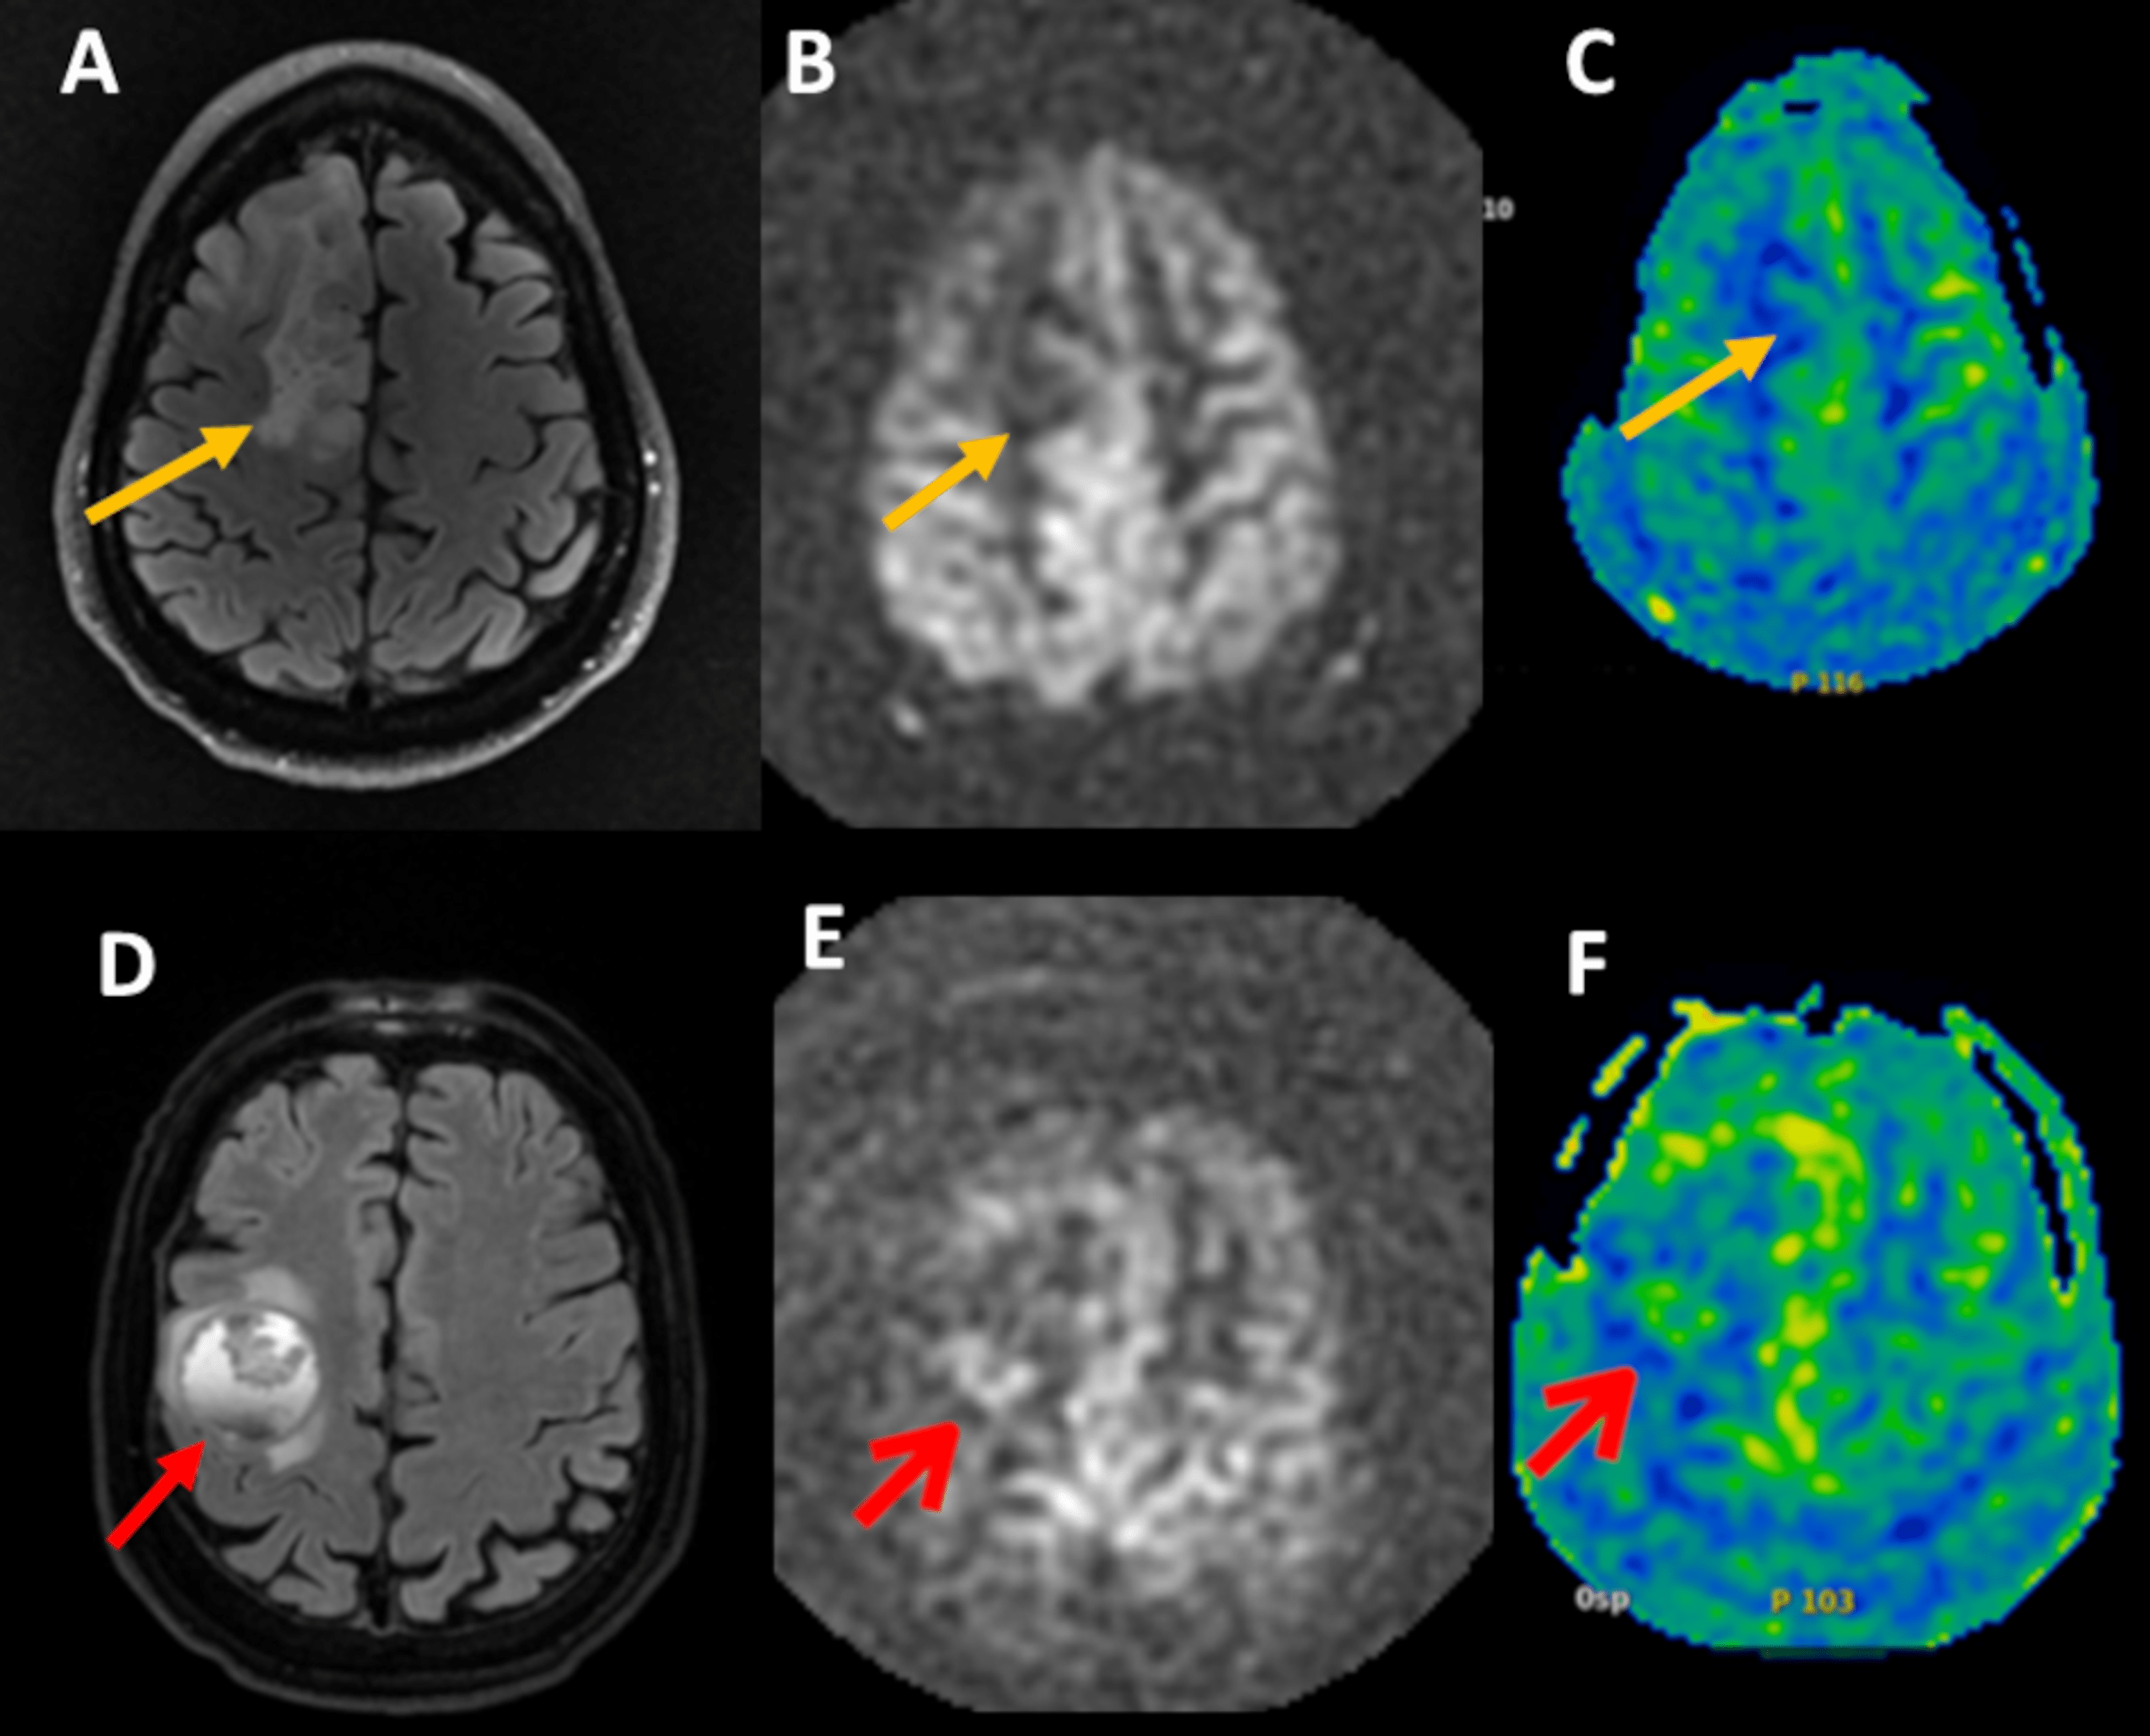

(A) T2 image of brain metastasis (axial view) showing a left parietal,... Download Scientific Markers Brain Metastasis Open in a new tab. Overview of the metastatic cascade: Conventional wisdom has rendered patients with brain metastases ineligible for clinical trials for fear that poor survival could mask the benefit of. Brain metastasis, which commonly arises in patients with lung cancer, breast cancer and melanoma, is associated with poor survival. In the present review, we summarize the current evidence. Markers Brain Metastasis.